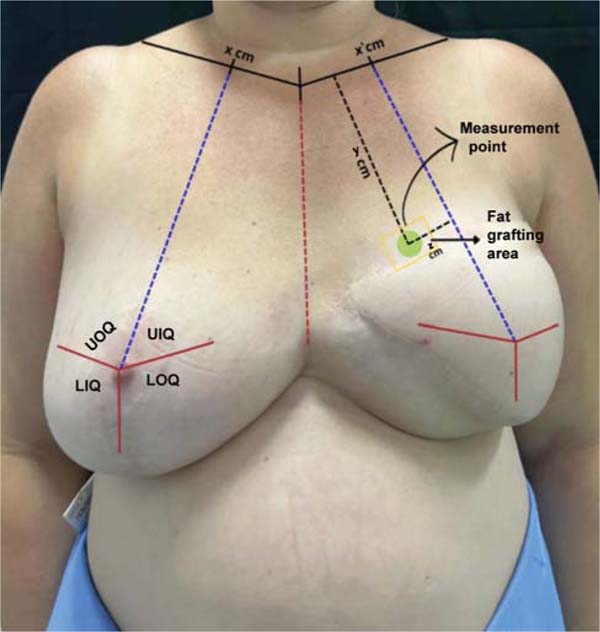

Preoperative marking and measurement point definition

First, the non-reconstructed breast is divided into four quadrants, using the nipple as a horizontal reference and a line from the midpoint of the clavicle to the inframammary fold as the vertical one. This midpoint is also marked on the contralateral clavicle to orient the reconstructed breast. The sternal notch defines the center of the chest. Using a 20-cm compass, the point of the original nipple is transferred to the reconstructed breast, guided by the sternal line, allowing the marking of the four quadrants on the reconstructed breast.

Within the breast quadrant with perceived low volume, a fixed point is established for measuring subcutaneous thickness during follow-up. This point defines the central region of the quadrant, and the shortest distances from it to the clavicle and to the nearest division of the breast quadrant are recorded for reproduction in subsequent measurements (►Fig. 1).